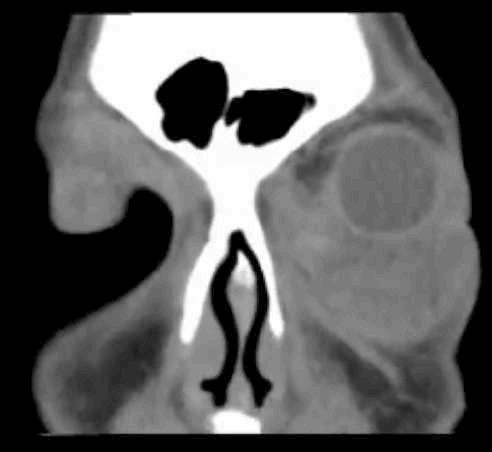

TAC (imagen B): Tumor de cuerpo carotídeo derecho, shamblin III

A B